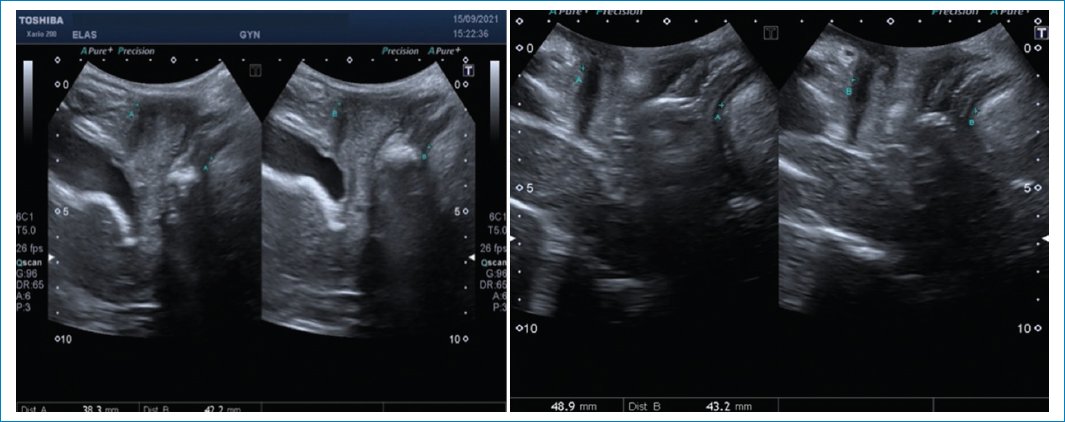

VEJIGA

• – Cistocele: con el examen físico solamente podemos evaluar un prolapso de la pared anterior de la vagina; sin embargo, con las imágenes podemos diferenciar entre un cistouretrocele que se asocia a incontinencia de orina y un cistocele con ángulo retrovesical intacto con síntomas de obstrucción al vaciado y baja probabilidad de incontinencia de orina. También puede ser que el prolapso de la vagina anterior sea por un divertículo uretral, quiste de Gartner o un enterocele anterior. El punto de corte para determinar el descenso de la vejiga es 10 mm por debajo de la línea pubiana que se traza perpendicular a la sínfisis pubiana3 (Fig. 7).

Figura 7. Se observa un descenso de la pared posterior vesical por debajo de la línea pubiana, con ángulo retrovesical cerrado.